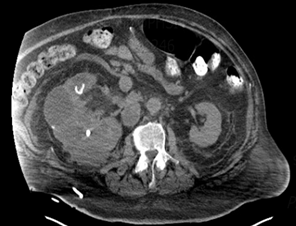

Figure 1. Computed tomography of the abdomen and pelvis with oral contrast.

Showing multiple cystic and solid appearing areas, dense

calcifications in the inferior aspect.

was done, computed tomography (ct) of the abdomen and pelvis without

intravenous contrast due to the impaired renal function, showed abnormal

appearing right kidney, with multiple cystic and dense appearing regions

measuring 17 cm in length, with retroperitoneal, enlarged lymph nodes adjacent

to the ivc up to 3 cm.